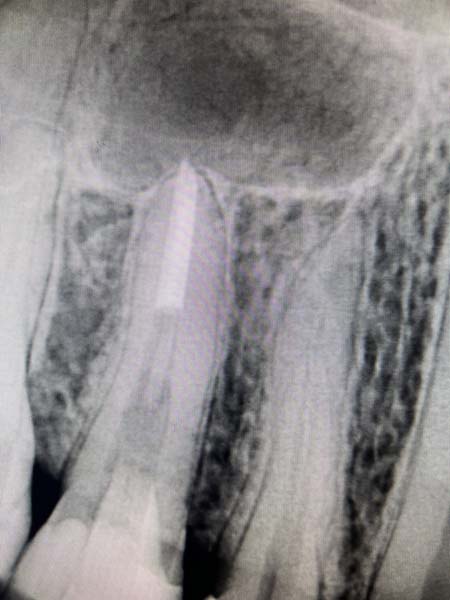

Менеджмент сепарованих ендодонтичних інструментів

"Менеджмент сепарованих ендодонтичних інструментів"

Як не ламати інструменти в кореневих каналах: причини та фактори ризику?

Сепаровані файли і прогноз ендодонтичного лікування: доказова база

Детальний розбір методів вилучення сепарованих ендодонтичних інструментів з кореневого каналу (з мікроскопом і без)

Коли ризик перевищує користь: в яких випадках вилучені інструменти ліпше не вилучати із кореневого каналу? Що робити з ускладненнями при вилученні сепарованих ендодонтичних інструментів?